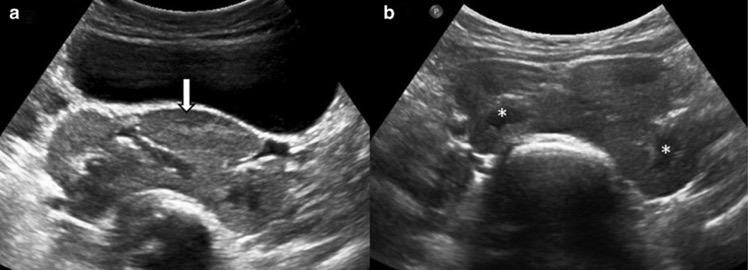

1. Pseudotumeurs rénales développementales

- Colonne proéminente de Bertin

- Lobulation fœtale persistante

- Rein dromadaire